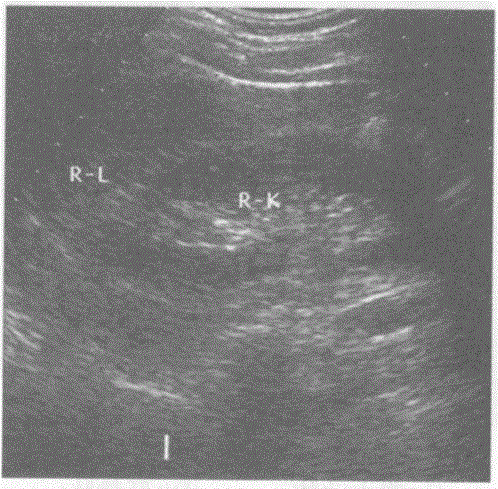

问题 请回答下图是采用哪种肝脏扫查方式:

选项 A.脾-肾纵切声像图 B.肝-肾纵切声像图 C.肝-一胃纵切声像图 D.肝-胆囊纵切声像图

答案 B